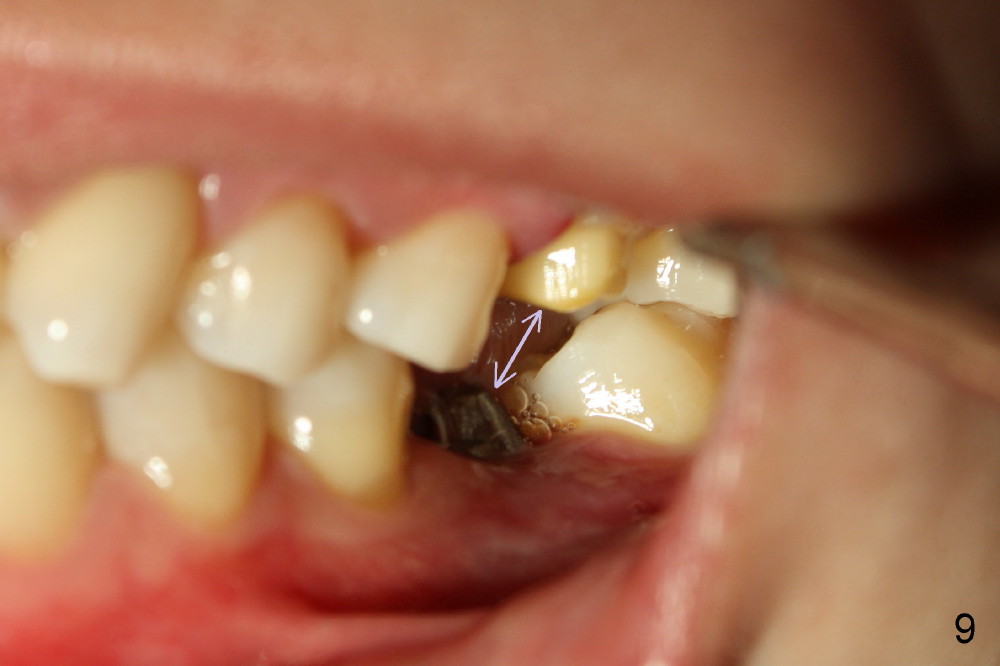

两周后,右下牙冠粘固,稍微调合,牙冠合面就穿孔了,向病人赔礼道歉,只好再预约重做,病人不满意的地方是牙冠与邻牙之间食物坎塞,重做牙冠还可能不能解决问题,只有矫正才能改变牙齿位置,倾斜度,而改正牙齿之间接触关系。不过先做左上,左下牙冠,制作也不容易,图六显示术前左上第一磨牙(*),好像supraeruption不厉害,但是咬合观显示左上第一磨牙的确往下移动不少(图七),星号(*)代表左下临时牙冠。没有任何其它选择,只好大刀阔斧磨左上第一磨牙(图八),这次大刀阔斧心情可不好,很辛苦。检查咬合,发现上下空间太大了(图九箭头),上次磨下颌基牙时太过分了。